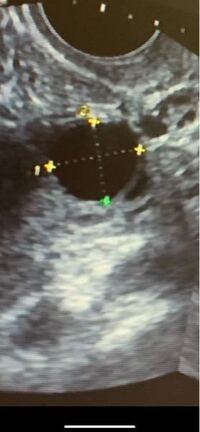

みんなの排卵時の卵胞の大きさは 卵胞チェックで分かるの 妊活ボイス

卵胞チェックに行き前回12mm 今回育ってて良かったあ 15 8mm Yahoo 知恵袋